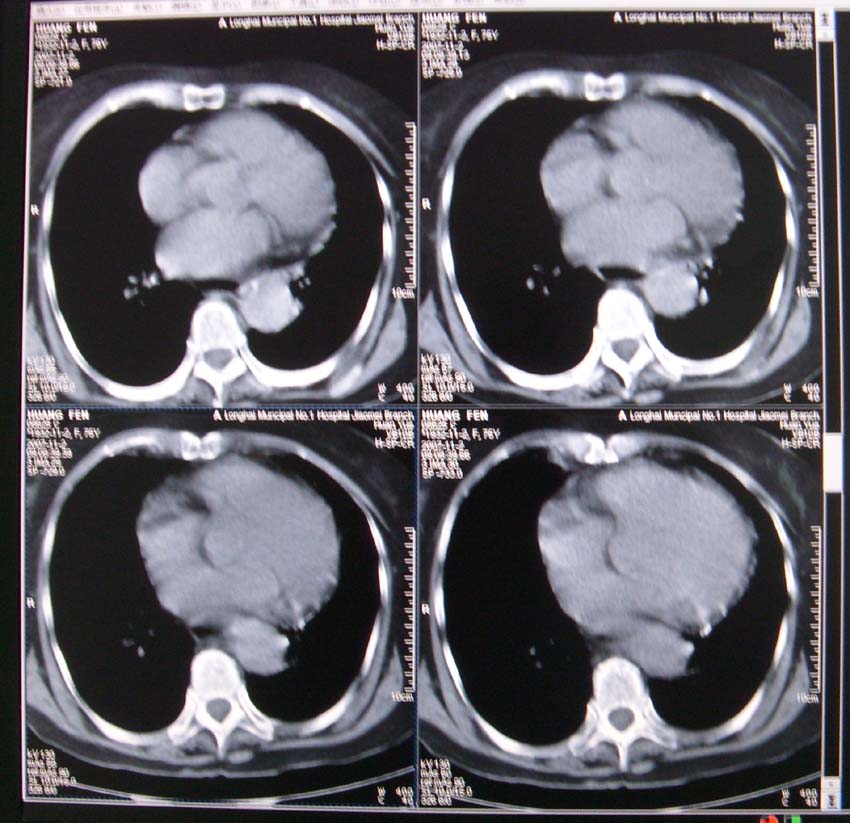

以下是引用xiaoniu在2007-11-4 12:05:00的发言:[br]这是胸主动脉迂曲延长造成的下段向右移行的影像表现,应该是:胸主动脉移行段。[br]

以下是引用nanjing在2007-11-4 12:21:00的发言:[br]降主动脉迂曲移位。